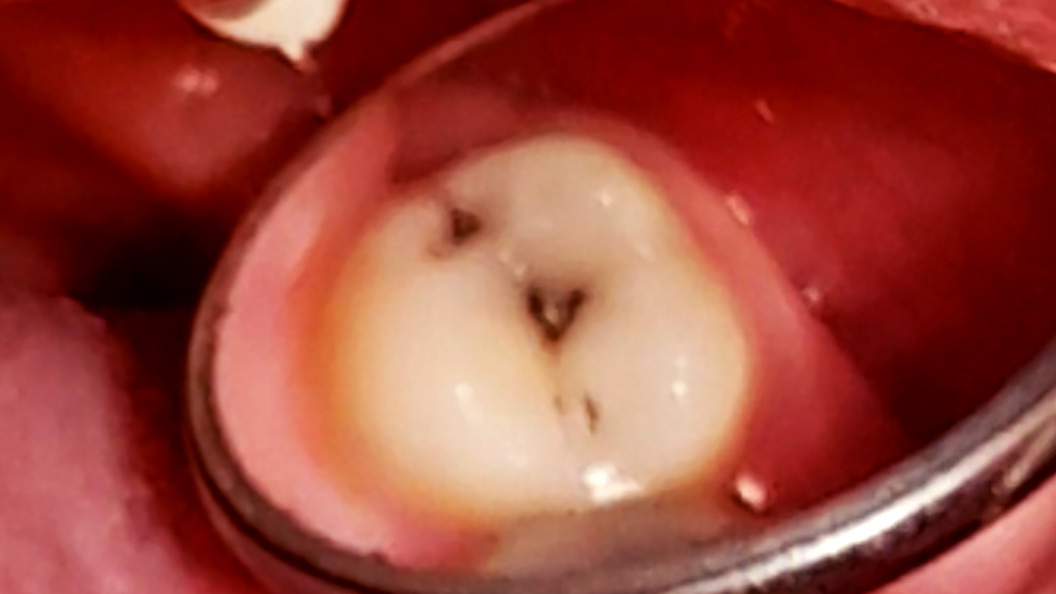

В «Стоматологию Комфорта» обратилась пациентка с жалобами на кратковременные боли от приёма холодных продуктов в области 27 зуба. В ходе осмотра врачом-стоматологом-терапевтом Похилько Н. Г. была обнаружена кариозная полость на жевательной поверхности 27 зуба. Зондирование было болезненно, перкуссия не вызвала реакции. Похилько Н. Г. провела ревизию и обработку полости под контролем кариес-маркера. Был поставлен диагноз: хронический глубокий кариес 27 зуба окклюзионно. Врач принял решение о лечении кариеса с установкой пломбы из материала Estelite.

- препарирование кариозной полости под контролем кариес-маркера;